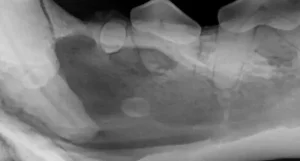

Los Algodones, a small town on the border of Mexico and the United States, has become a popular destination for dental care, drawing over a